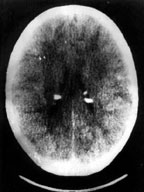

| Рисунок 5. Компьютерно-томографическое исследование головного мозга |

Субэпендимальные узлы встречаются в 95% случаев и выявляются как при компьютерном томографическом (КТ), так и при МРТ-исследованиях мозга. Субэпендимальные узлы в большинстве случаев множественные, прилегающие друг к другу. Локализуются, как правило, в стенках боковых желудочков, реже — в стенках III и IV желудочков мозга. При локализации в стенках боковых желудочков субэпендимальные узлы глубинной частью могут внедряться в хвостатое ядро или таламус. Форма субэпендимальных узлов обычно округлая или вытянутая. По мере роста ребенка в субэпендимальных узлах происходит постепенное отложение кальция. На компьютерных томограммах доминирующим признаком заболевания являются множественные, полностью или частично кальцифицированные, субэпендимальные узлы округлой формы, локализующиеся в стенках боковых желудочков (рис. 5). КТ-исследование более чувствительно, когда речь идет о выявлении кальцифицированных субэпендимальных узлов.